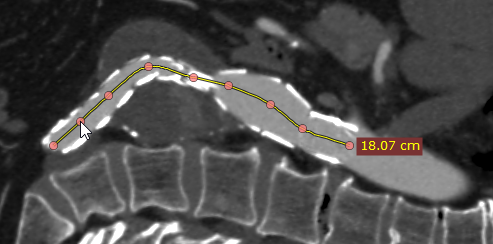

点击鼠标左键放置起始节点,重复此操作沿要测量的结构放置其余节点。

绘制开放多边形

如有需要,绘制完成后可以修改形状。双击图像完成绘制。